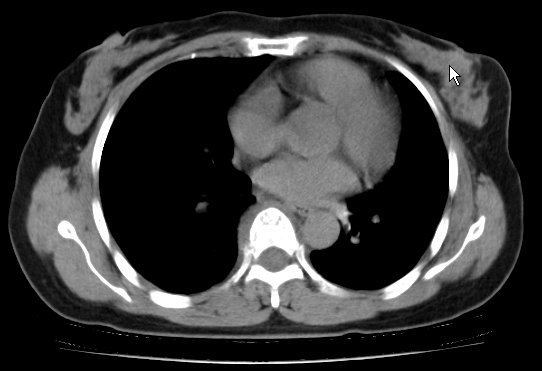

标题: CT25227:背部疼痛伴双侧胸壁痛2月,食欲差。 [打印本页]

标题: CT25227:背部疼痛伴双侧胸壁痛2月,食欲差。

肺结核并胸椎结核?请各位高手指教。

用椎体的条件来扫胸椎呀!考虑1左侧胸膜小结节形成2椎体结核并冷脓肿形成

考虑胸椎结核并椎旁软组织肿胀。

左肺结核灶,胸椎结核并冷脓肿。

左肺结核灶,胸椎结核并冷脓肿

椎旁软组织肿胀。